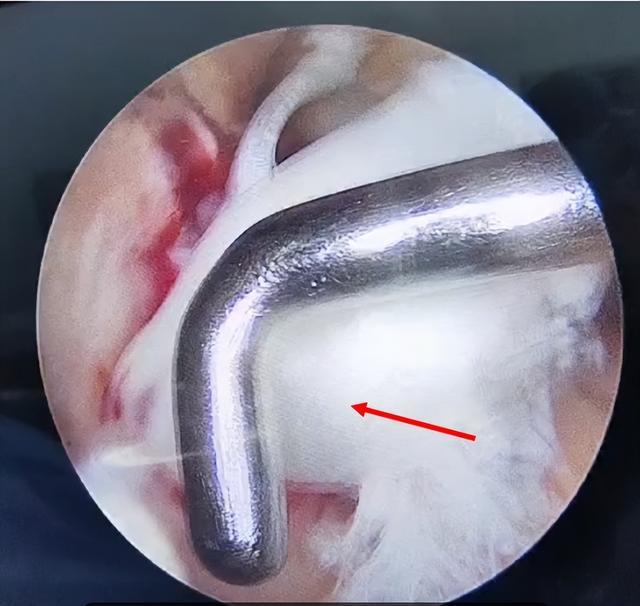

(关节镜下韧带完全断裂)

肖勇医师带领运动医学团队成功为患者实施了膝关节镜下前交叉人工韧带重建术。术中关节镜下探查:前交叉韧带完全断裂。在关节镜下引导,精准建立股骨胫骨隧道,引入直径7.5毫米人工韧带,镜下调节韧带张力,予以钛合金挤压钉固定人工韧带两端,手术仅仅通过三处不足2厘米的切口就恢复了膝关节的稳定性。